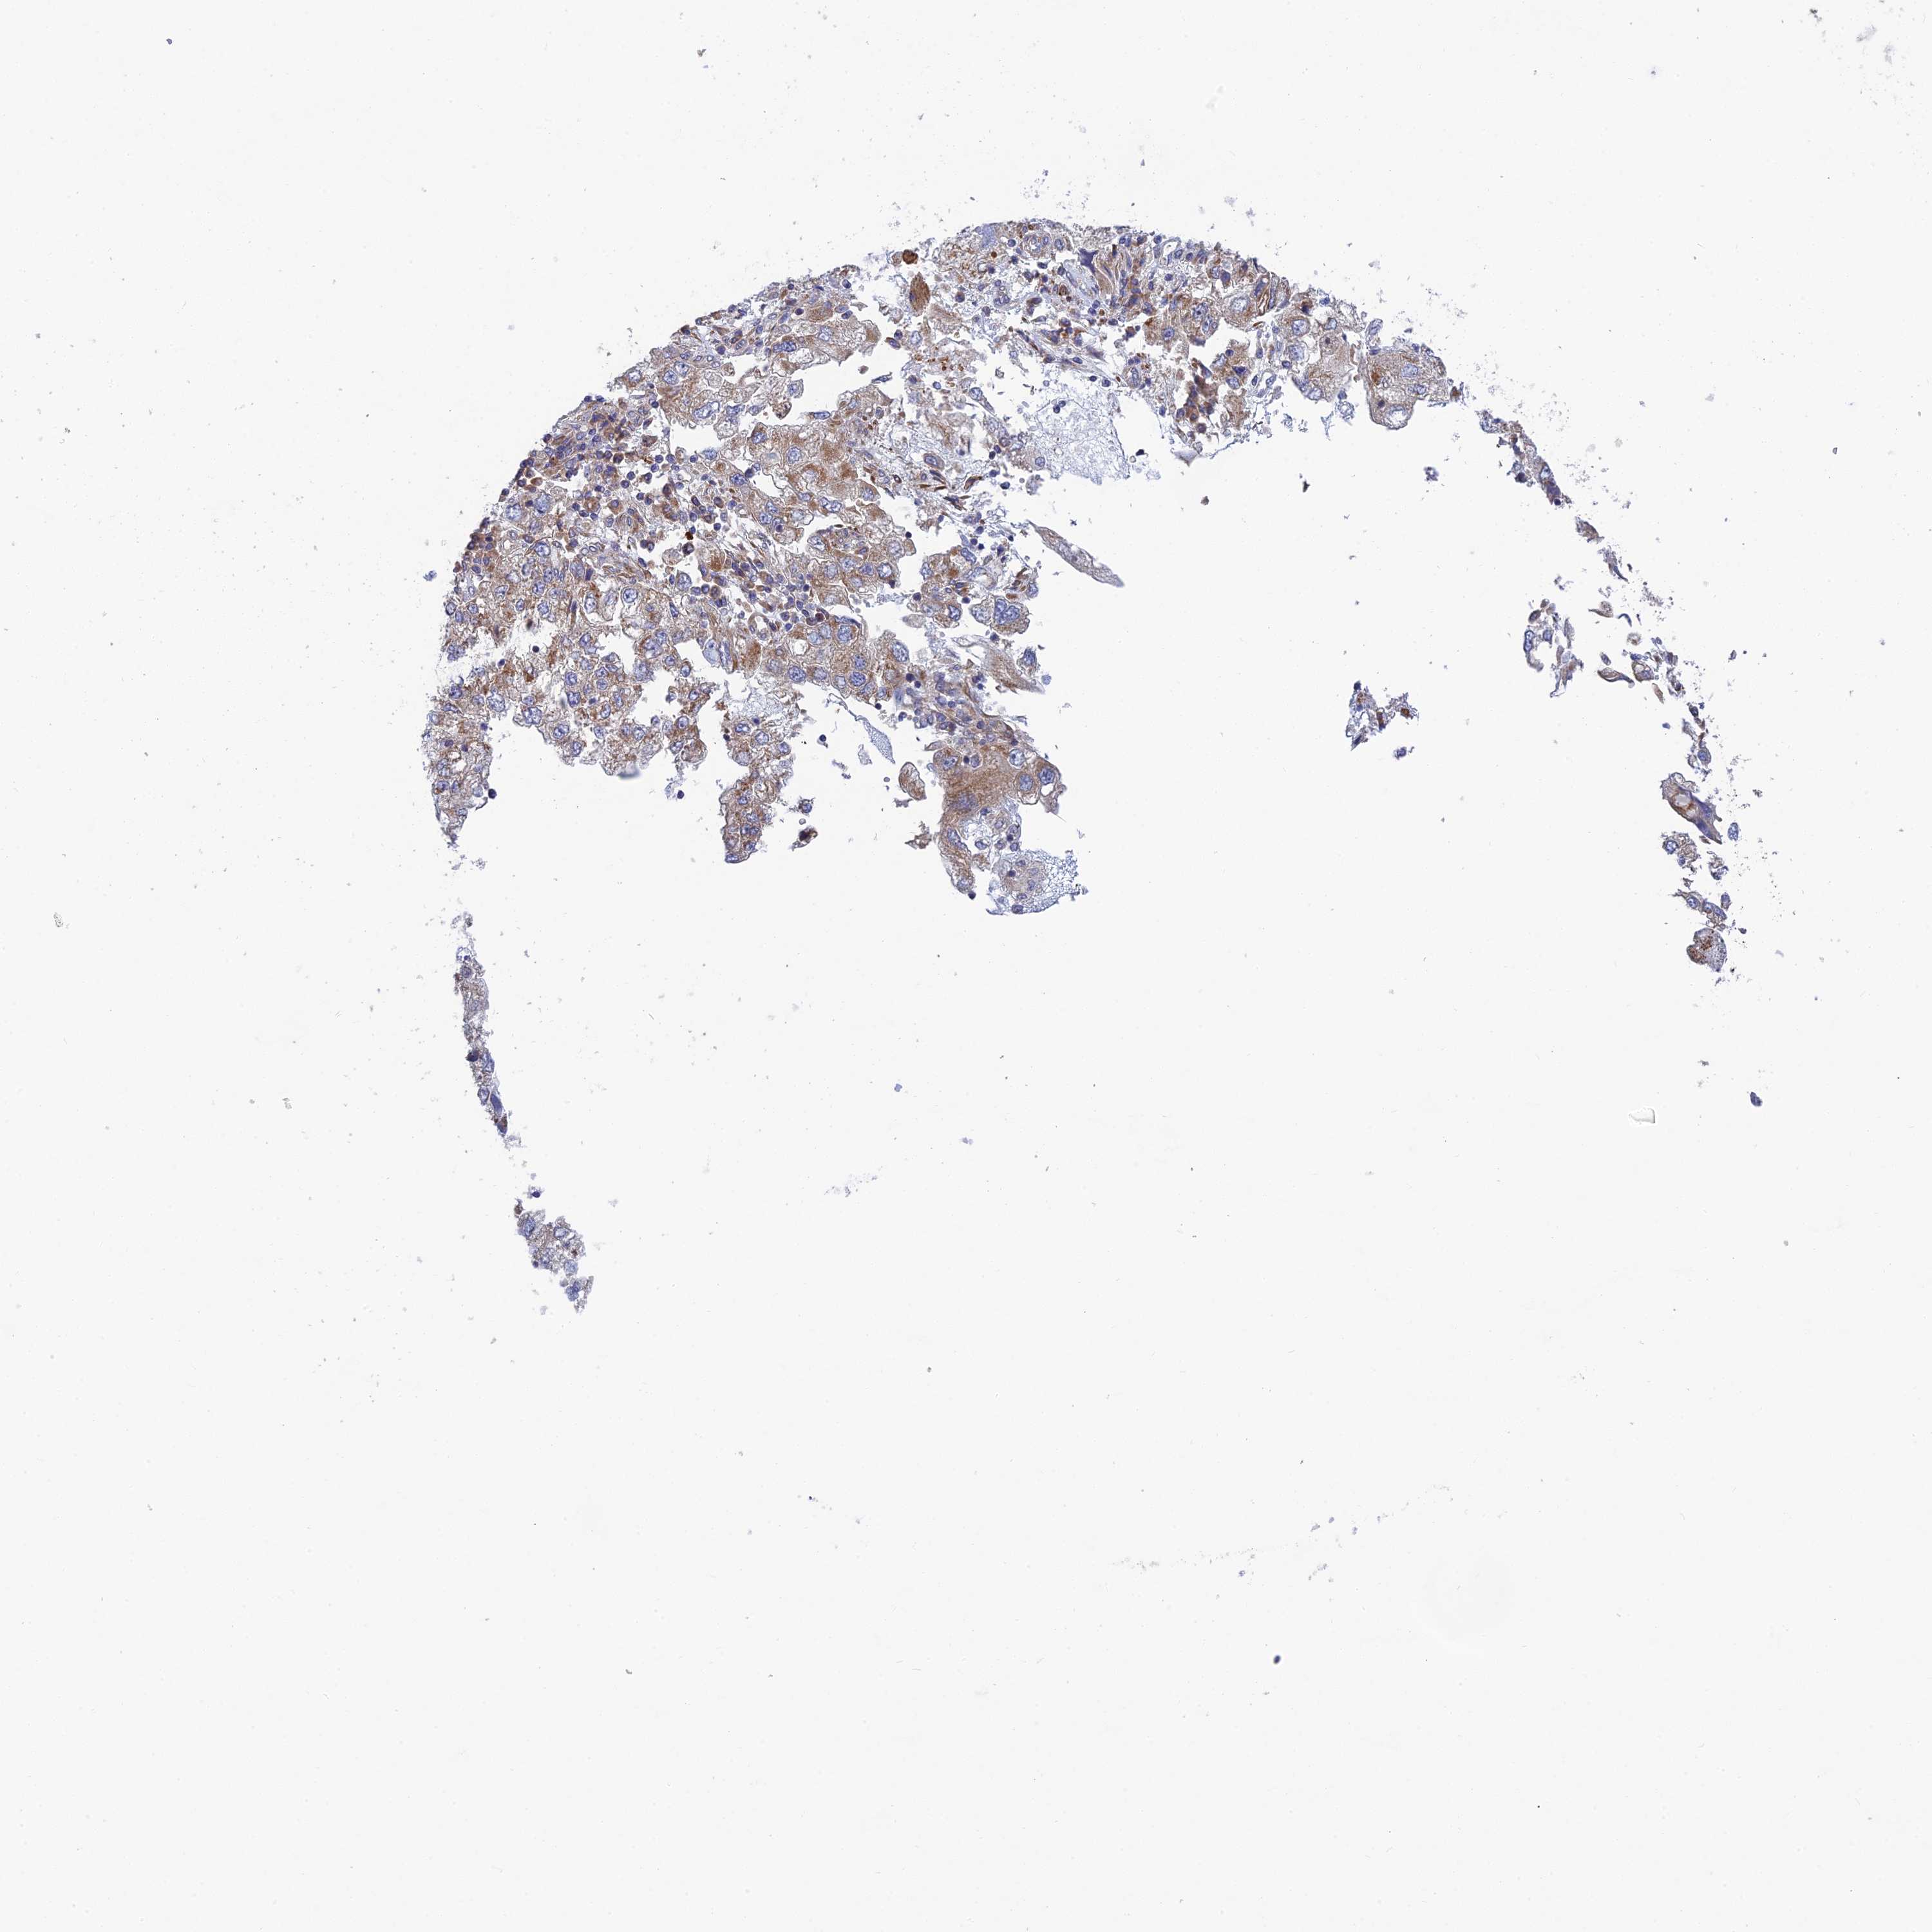

ENDOMETRIAL CANCER - Protein expressioni

A mouse-over function shows sample information and annotation data. Click on an image to view it in a full screen mode. Samples can be filtered based on level of antibody staining by selecting one or several of the following categories: high, medium, low and not detected. The assay and annotation is described here.

Note that samples used for immunohistochemistry by the Human Protein Atlas do not correspond to samples in the TCGA dataset.

Antibody stainingi

Antibody staining in the annotated cell types in the current human tissue is reported as not detected, low, medium, or high, based on conventional immunohistochemistry profiling in selected tissues. This score is based on the combination of the staining intensity and fraction of stained cells.

Each image is clickable and will lead to virtual microscopy that enables deeper exploration of all samples and also displays staining intensity scores, fraction scores and subcellular localization as well as patient and tissue information for each sample.

Antibody HPA044359

Staining

High

Medium

Low

Not detected

Intensity

Strong

Moderate

Weak

Negative

Quantity

>75%

75%-25%

<25%

None

Location

Nuclear

Cytoplasmic/membranous

Cytoplasmic/membranous,nuclear

Adenocarcinoma, NOS

Adenocarcinoma, metastatic, NOS